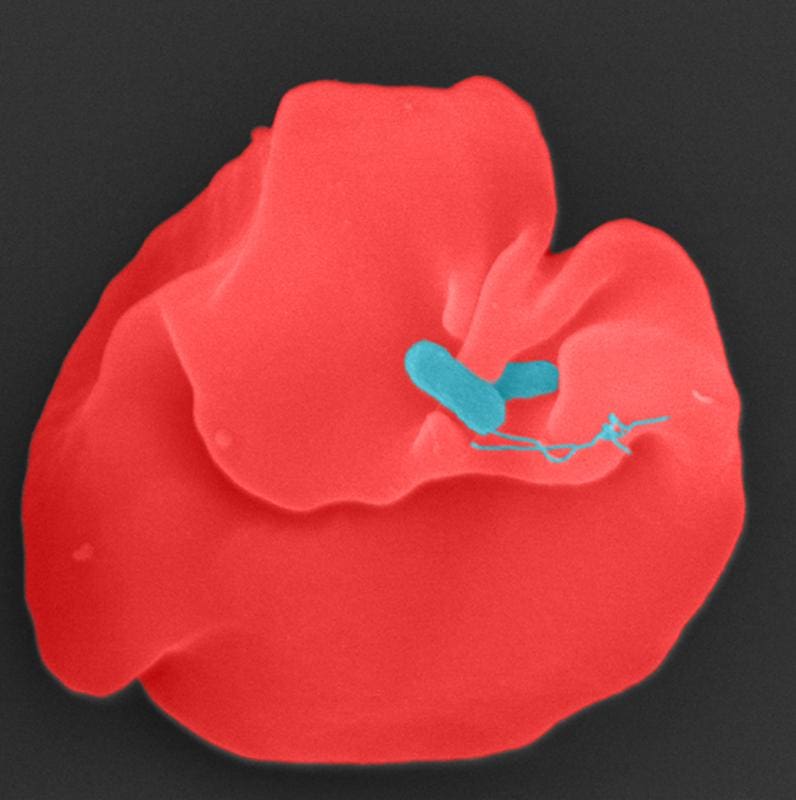

Researchers at the University Medical Center Frankfurt have elucidated the mechanism of the deadly infectious disease Oroya fever, which is caused by the bacterium Bartonella bacilliformis. They identified two proteins responsible for destroying red blood cells and found an inhibitor that stops this process in the lab. The results could lead to a novel treatment that circumvents resistance.

An international team led by the director of the Institute of Medical Microbiology and Hospital Hygiene analyzed over 1700 genetic variants of the bacterium. They discovered a porin protein that enables exchange with the environment and an enzyme called alpha-beta hydrolase. Both proteins work together and cause hemolysis. Structural analyses and targeted mutations proved that the enzymatic activity of the hydrolase is crucial. This makes the enzyme a potential target for drugs.

In laboratory experiments, a phospholipase inhibitor blocked hydrolase activity and prevented the destruction of blood cells. Such a therapy could minimize resistance, as it directly attacks the disease-causing effect of the pathogen. The disease kills hundreds in South America every year, often unnoticed by the world public, and is poverty-related.